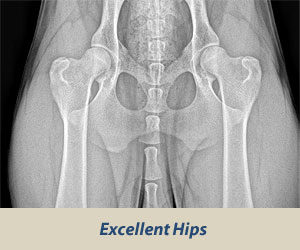

While the OFA classifies hips into seven different categories: Excellent, Good, Fair (all within normal limits), Borderline, and then Mild, Moderate, or Severe. The last three are considered dysplastic. Let’s take a closer look:

The most effective way to diagnose hip dysplasia is with a radiograph or X-ray.

Your veterinarian will x-ray your dog’s hips to determine the degree and severity of hip dysplasia. Only then they’ll be able to determine the best course of treatment for your dog.